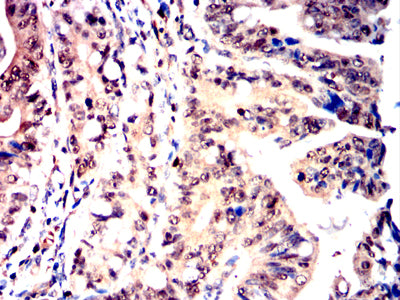

Product Image

- Immunohistochemical analysis of paraffin-embedded human rectum cancer tissues using NPM3 mouse mAb with DAB staining.